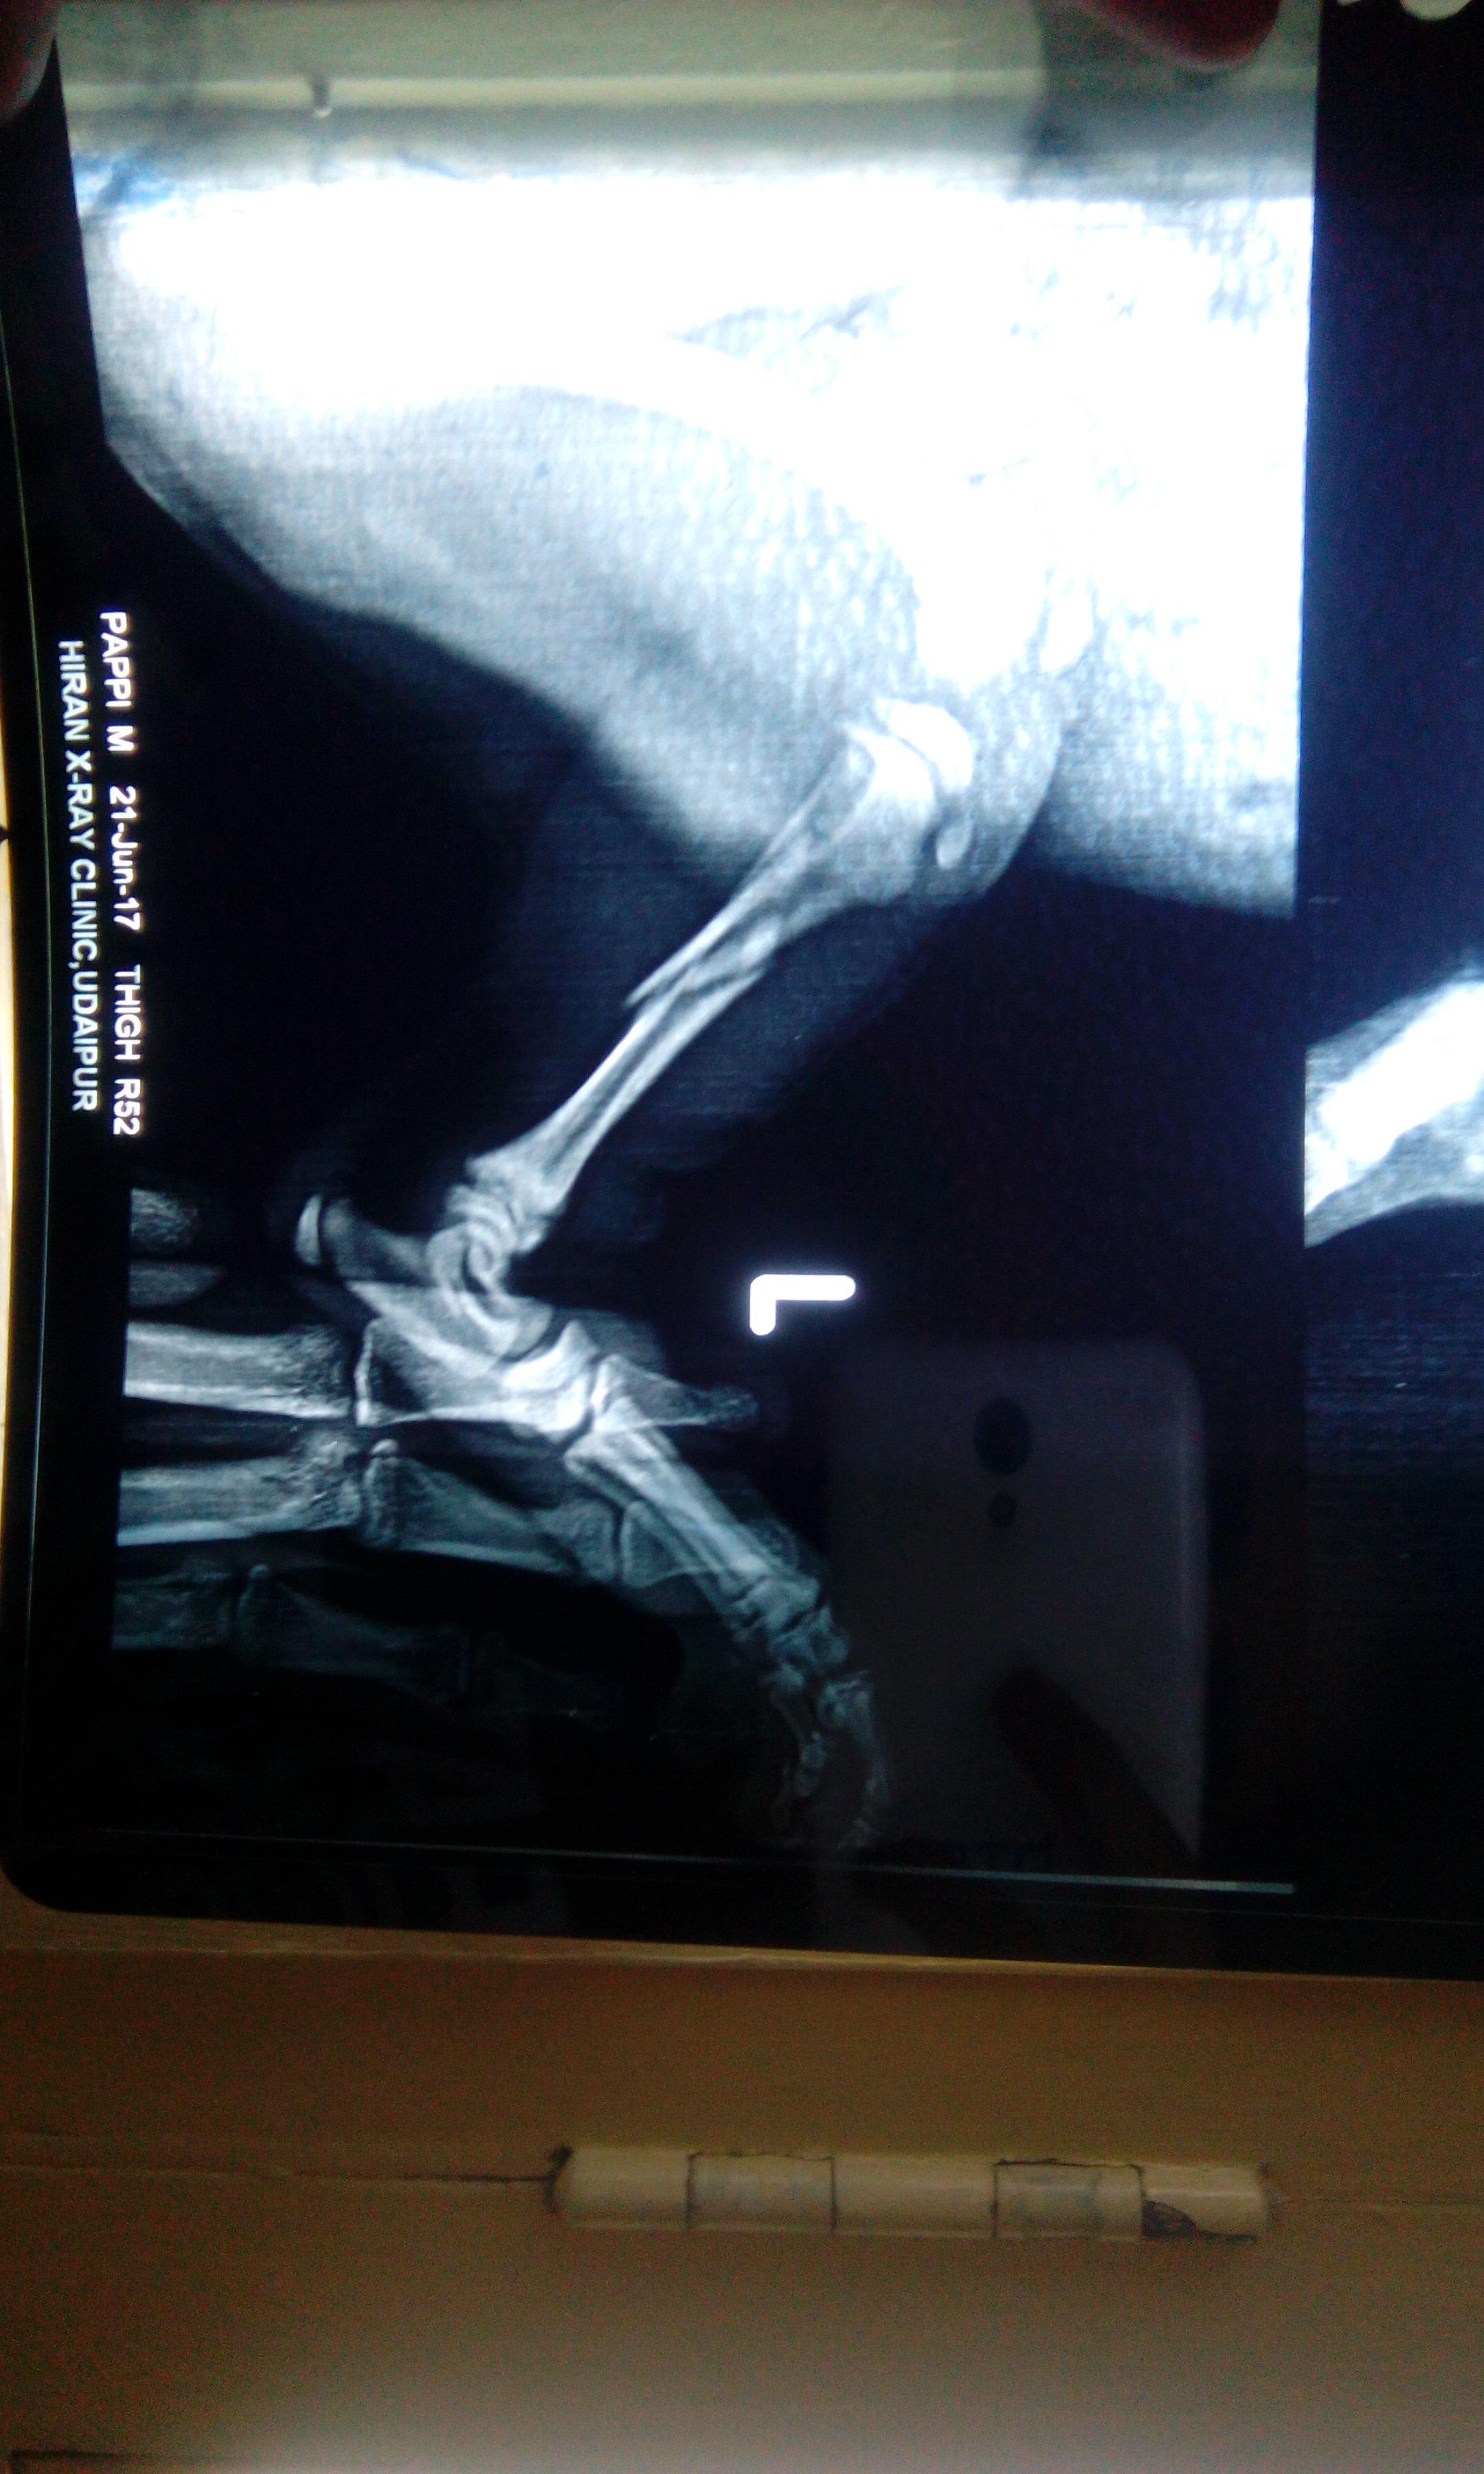

My pug, 2 months old, slipped from my hands and broke his left lower limb. I took 3 different vet consultations all in vain. His plasters slip off and its very hard to put up something that keeps his leg straight. We confined him to a little cage to not let him run. He is keeping his foot on the ground now after 7 days from the injury and we aren't tying up any bandages buy are giving him supplements. Will he be able to walk again without any deformity?

That really depends on how the fracture heals. If the splint/bandage falls off then you could take him to an orthopedic surgeon who could pin or plate the fracture internally so he wouldnt need an external splint/bandage.

Ouch, poor Scooter! It looks like a painful break, and unfortunately only time will tell if his leg will heal properly or not. Keeping him confined to a cage is a good idea to make him rest fully, and I would only take him out to go to the bathroom and then bring him right back inside to the cage. If you can't keep the leg immobilized, then it may not grow back correctly but again only time will tell. I'm not sure what supplements you are giving him, but please be very careful when doing that; in fact, I wouldn't recommend it unless your vet told you to give them to Scooter. Too many supplements in a growing puppy will cause health problems such as developmental abnormalities from too much calcium. That's why it's never recommended to give a puppy vitamins. If your vet hasn't told you to give these supplements, I would check with them that it's ok for Scooter to receive them.